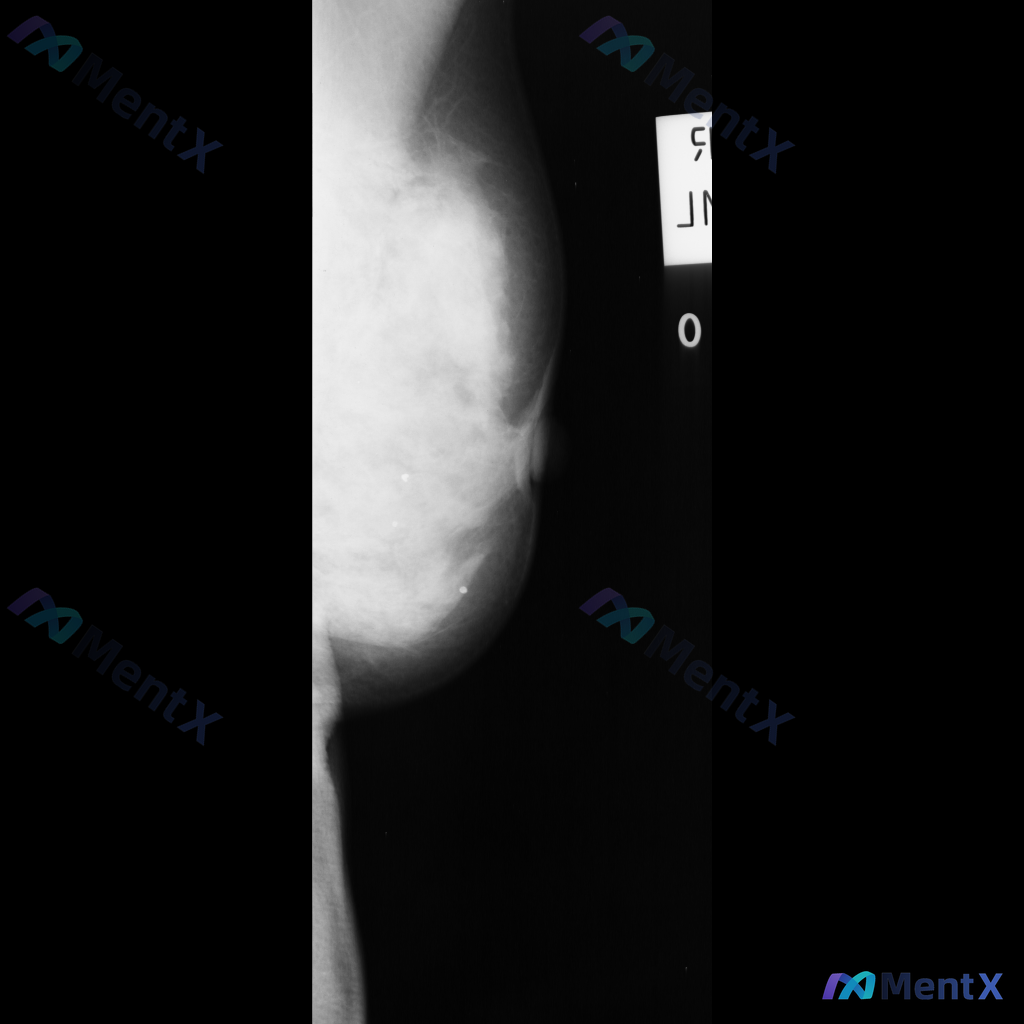

整理到一份乳腺钼靶影像的病例资料,先跟大家同步下目前的表现: - 检查部位:右侧乳腺 - 背景腺体:ACR BI-RADS C型(不均匀致密型) - 异常区域:右乳腺中上部腺体组织内 - 核心征象: 1. 可见一个不规则形的高密度肿块 2. 肿块边缘不清晰,呈毛刺状 3. 肿块周围的乳腺正常结构有牵...